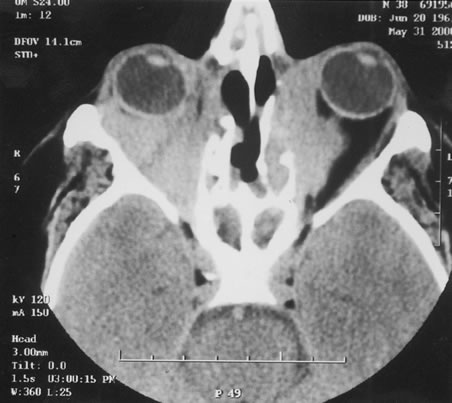

The finding of retinal vascular changes in patients with SLE correlates with the activity of the disease.214 The relationship of cotton-wool spots alone to CNS lupus has been debated, but to date no relationship has been established. Most experts feel that the finding of cotton-wool spots does not indicate the presence of CNS lupus. A much less frequent, severe retinal vasoocclusive disease has been described and does appear to be associated with CNS lupus, in particular, diffuse CNS dysfunction, such as an organic brain syndrome.214–223 This more severe retinal vasoocclusive disease may present as a central retinal artery occlusion, central retinal vein occlusion, branch artery occlusion, or most frequently, a diffuse retinal vasoocclusive process (Fig. 5), sometimes called retinal vasculitis. Although this last process sometimes has been called retinal vasculitis, the exact pathogenesis may not be true vasculitis. Cases of severe retinal vasoocclusive disease in SLE in association with the lupus anticoagulant also have been reported, and the retinal disease in these cases is presumed to be secondary to this autoantibody (Fig. 6).190,191 The prognosis for vision with this diffuse retinal vascular disease is poor and retinal neovascularization commonly develops. Panretinal photocoagulation may be of value in the treatment of the neovascularization of severe lupus retinopathy. Approximately 50% of eyes affected with this severe vaso-occlusive disease become blind. Although visual loss is common in those patients with severe retinal disease, in the more common mild retinopathy visual loss is unusual.223

Fig. 5. A. Fundus photograph and B. fluorescein angiogram, demonstrating diffuse vaso-occlusive disease in a patient with systemic lupus erythematosus. Fluorescein angiogram shows extensive nonperfusion of the retina. (Jabs DA, Fine SL, Hochberg MC, et al: Severe retinal vaso-occlusive disease in systemic lupus erythematosus. Arch Ophthalmol 1104:558, 1986. Copyrighted 1986, American Medical Association. Reprinted with permission.)